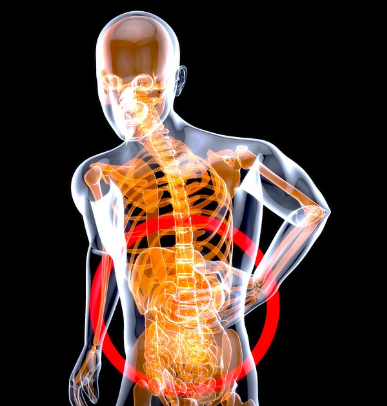

간은 몸의 오른쪽 상복부, 즉 오른쪽 갈비뼈 아래에 위치해 있어요. 위장과 장기들 사이에 넓게 퍼져 있으며, 정상적인 경우에는 외부에서 직접 만져지지 않죠. 하지만 염증이나 지방간, 간비대 등으로 크기가 커지면 압박감이나 묵직한 통증을 느끼게 됩니다. 간 통증은 대부분 '둔하고 무거운 느낌'으로 나타나는 것이 특징입니다.

오른쪽 옆구리 통증의 대표 원인

- 지방간, 간염 등 간 자체의 이상

- 담낭염, 담석증 같은 담도계 질환

- 늑간 신경통 또는 갈비뼈 타박상

- 대장 가스 정체로 인한 복부 팽만